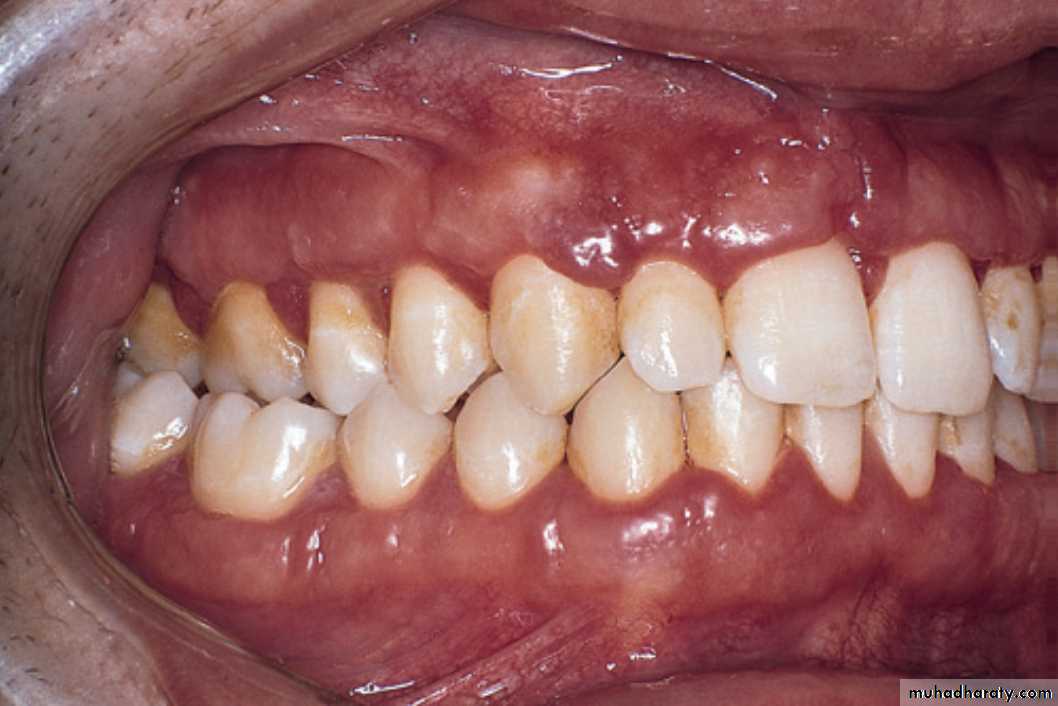

Soft nodular thickening of the oral mucosa is a typical feature and, in this case, was associated with facial swelling and intermittent diarrhea.Crohn’s disease

The gingivae are hyperplastic and irregular and erythematous. These changes are obvious, but more subtle signs are easily missed. The appearances are identical to those in sarcoidosis in the gingivae.THE END